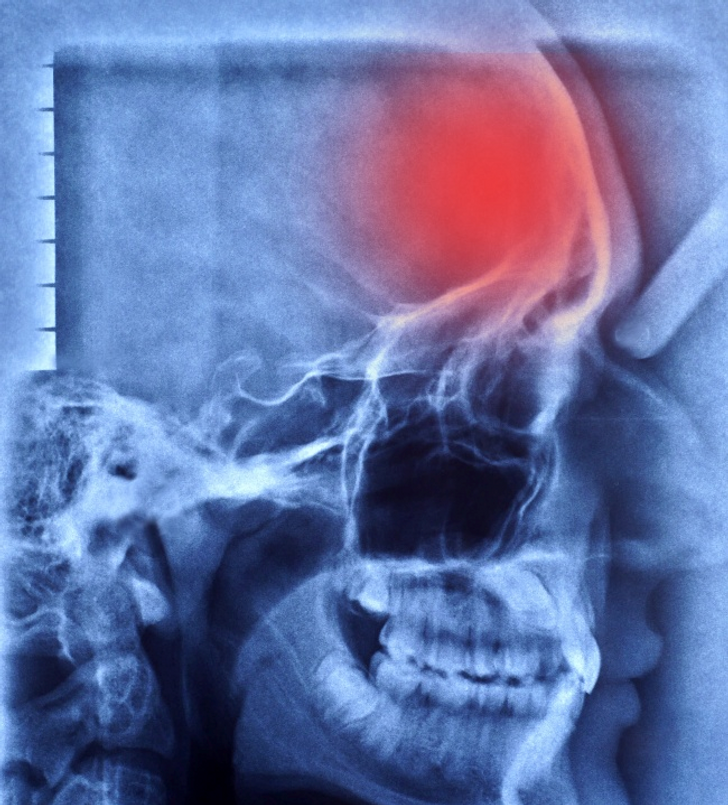

По данным Всемирной организации здравоохранения, инсульт находится на третьем месте в списке самых смертоносных заболеваний и расстройств. К сожалению, большинство инсультов даже не замечаются, пока не становится слишком поздно. Команда DGRADgruop хочет показать вам, как распознать инсульт и как предотвратить его отнятие жизни. Врачи выделяют два типа инсультов: геморрагический инсульт и ишемический инсульт, вызванный закупоркой сосудов. Ишемический инсульт не может иметь четких симптомов и может легко остаться незамеченным. По статистике, 80% инсультов приходится на ишемический тип. 37% этих больных инсультом умирают, 31% тех, кто перенес инсульт, нуждаются в постоянном уходе, а 20% не могут самостоятельно ходить после него. Что происходит во время инсульта? Наиболее распространенной причиной ишемического инсульта является тромб или спазм, который блокирует кровоток в определенной части мозга. Ткань вокруг свернувшегося сосуда набухает, и пространство в черепе ограничено. Повышае

По данным Всемирной организации здравоохранения, инсульт находится на третьем месте в списке самых смертоносных заболеваний и расстройств. К сожалению, большинство инсультов даже не замечаются, пока не становится слишком поздно.

Врачи выделяют два типа инсультов: геморрагический инсульт и ишемический инсульт, вызванный закупоркой сосудов.

По статистике, 80% инсультов приходится на ишемический тип. 37% этих больных инсультом умирают, 31% тех, кто перенес инсульт, нуждаются в постоянном уходе, а 20% не могут самостоятельно ходить после него.

Наиболее распространенной причиной ишемического инсульта является тромб или спазм, который блокирует кровоток в определенной части мозга. Ткань вокруг свернувшегося сосуда набухает, и пространство в черепе ограничено. Повышается внутричерепное давление, появляется головная боль.

Весь мозг страдает от высокого давления. Во время инсульта руки и ноги могут перестать двигаться, человек может потерять координацию или способность слышать или говорить. В некоторых случаях возможны даже галлюцинации.